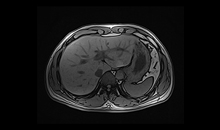

动态B0

涡流补偿技术

改善脂肪抑制效果,减小DWI图像伪影。改善SWI等对B0涡流敏感序列的图像质量